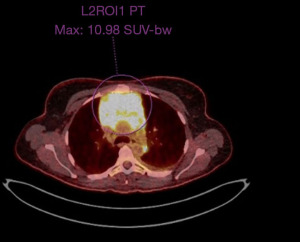

A thoracic computed tomography (CT) scan (Figure 2) revealed a large anterior-superior mediastinal mass of 80 mm × 67 mm with malignant left pleural effusion. The core biopsy was consistent with a myeloid sarcoma (MS), a rare extramedullary manifestation of acute myeloid leukemia (AML), according to World Health Organization (WHO) 2022 classification and the International Consensus Classification (ICC) 2022. The fluorine 18-labeled fluorodeoxyglucose (FDG) positron emission tomography (PET)-CT (Figure 3) showed increased FDG uptake by the mediastinal mass, the presence of numerous hypermetabolic lymph nodes on both sides of the diaphragm and a thickened left pleura. The bone marrow biopsy was negative for AML and a new large surgical biopsy of the mediastinal mass had to be performed for fresh tissue samples, in order to perform flow cytometry, molecular and cytogenetic analysis.